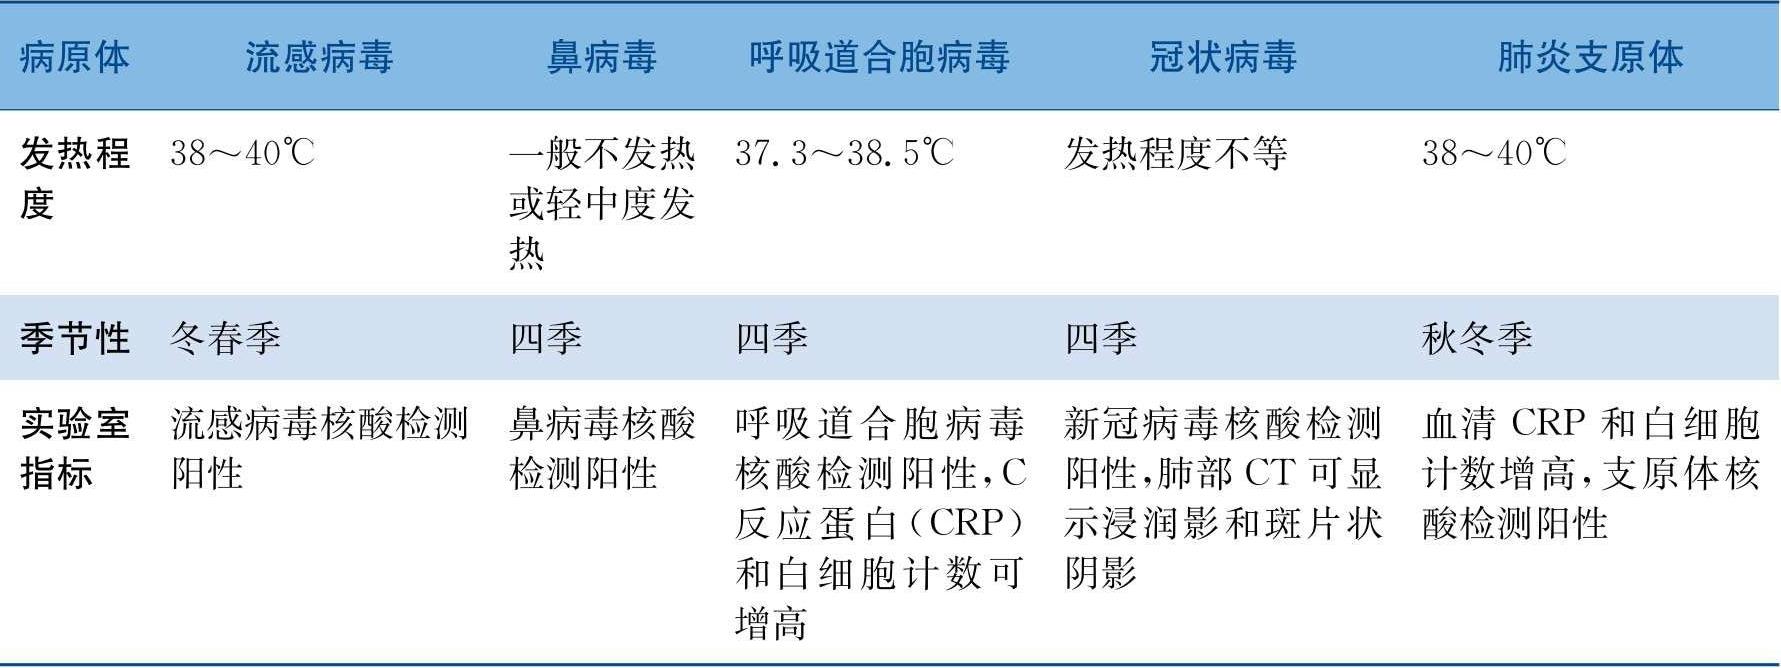

表1 不同呼吸道病原体的特点

续表